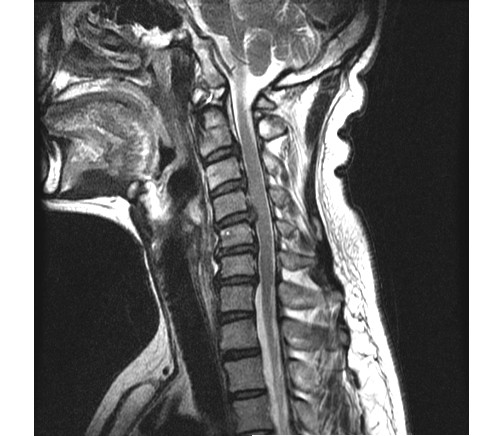

2013 2 ʴٸ 鼭 ѵ ӵǾ ȼ ִ 湮Ͽ а˻(MRI) ް, 㸮ũ Ű ִٴ ô ڼ, Ű漺ü ް ũ ٰ ĥ ڰ ʰ ̿ ణ ְ, ȿ Ÿ ĥ ȣ ٽ ġḦ Ҵ **** 湮Ͽ x-̿,MRIԿ غ ʿ Ʒ(4.5.6.7) 3 ũ Ƣ Ű ִٴ ¿ϴ. ſ Ͽ ٰ մϴ. ϴ Űֻ ġ Ÿ ¿, Ϻ ߷° ġḦ ̾ϴ. ġ Ŀ ° ȭǸ ñδ ھƼ ߺκ ִ ƾ ȴٰ ߽ϴ. ũ 500 ,ġ 2,500 ȴٰ ߽ϴ. üϿ콺 縦 ϴ 忡 Ŀ üϿ콺 ãƾ ߰ ϴ ϸ鼭 ͳݿ ڷḦ ã ߿ ڸǥغ ˰Եǰ Ͼ ʴ ʱ۵ 鼭 ʱ۵ ܼ ȸ Ͽ ڸǥغ ߽ϴ. ߰ ȸ ȭ ʰ Ͽ غ ξ ϰ پϴ. ڰ ʹ Ͼ ٽ þ ִ ȸ ȣ ȴ Ͽε ұϰ ݹ ȭ Խϴ. ̰ ð ϰ ʰ Ȱ ɴ ڼ ϴ. ϴ ÿ پ ϴ. ͳݿ ** ˷ֽôµ ϰ ƮĪ ̾ϴ. ȸ ó Ȯϰ ϴ Դϴ. ȭȭ ˷ֽôµ Ȯϰ ִ ͵ ű߽ϴ. ǻ ֽð ı ̶ ϴ ϸ鼭 ߰ 30ʾ ϶ ߽ϴ. ῡ ٽϰ ƮĪ ȿ ϰ ٲ۴ٰ ϼ̽ϴ. 鿡 ϴٰ ְų ִ پ ̶ ϸ ȭֽŴٰ ߽ϴ. ̰ͱ ħ ̾ϴ. ῡ Ϸ ϰ ῡ ȸԲ ڷ 帰 Դϴ. ȸԲ ˷ֽ ϸ鼭 ƴ غ ° Ǵ ȭ Դϴ. õ Կ ſ 鿡 ϴ ֽ ڼ Ϸ ϴ, ణ Ÿ° ʹٰ ߽ϴ. ʰ ,Ŀ ƿͼ õ κ(12).Ӹ(8) غ Բ , ȵ ణϰ Ÿ., ⺻ Ӹе 9 غ 30 ǻϴ. Ӹκ 9е ؼ ϰ ֽϴ. ߽ϴ. ȭ ּ̽ϴ. ǻͿ ɾƼ mriϰ Ͽ 帮 Ű澲ٰ ٽ ͽϴ. ȸԲ ʰ ǻ ϴ¹ ˷ֽʴϴ. ǻ տ Ȳ ʰ ɴ ڼ ٲٴϱ ϴ. űԿ ڼ ߿ ƮĪ ü ߿伺 ű ȵ ߽ϴ. ʰ ȸϴ е ʱ۵ ó Ե Ͼ ̷ο Բ ʾƵ ǰڴٴ 밨 ϴ. mri ½ϴ. ȸԲ Ȯϰ Ǵϰ ٽ ȮҶ Ʒ mri øŴϴ. ø Ȯֽð Ź帳ϴ. ---------------------------------------- -- û Ȯϱ Ͽ mri øϴ. |